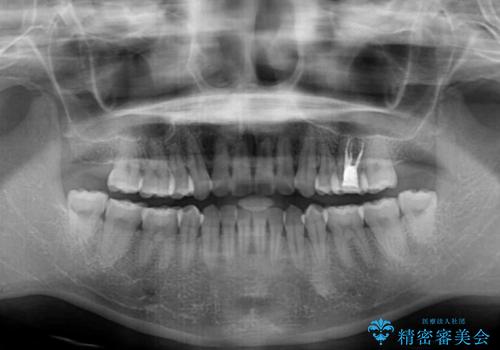

- 高校生の時に矯正治療を行ったものの、後取りをしてしまったとのことで来院された患者様です。

舌の突出癖が原因で後戻りをしたため、舌のトレーニングをしっかりと行っていただき、口元の突出感を改善することができました。

インビザラインの装着時間が守れず、1年強で終わる予定でしたが、4年間を要することとなりました。